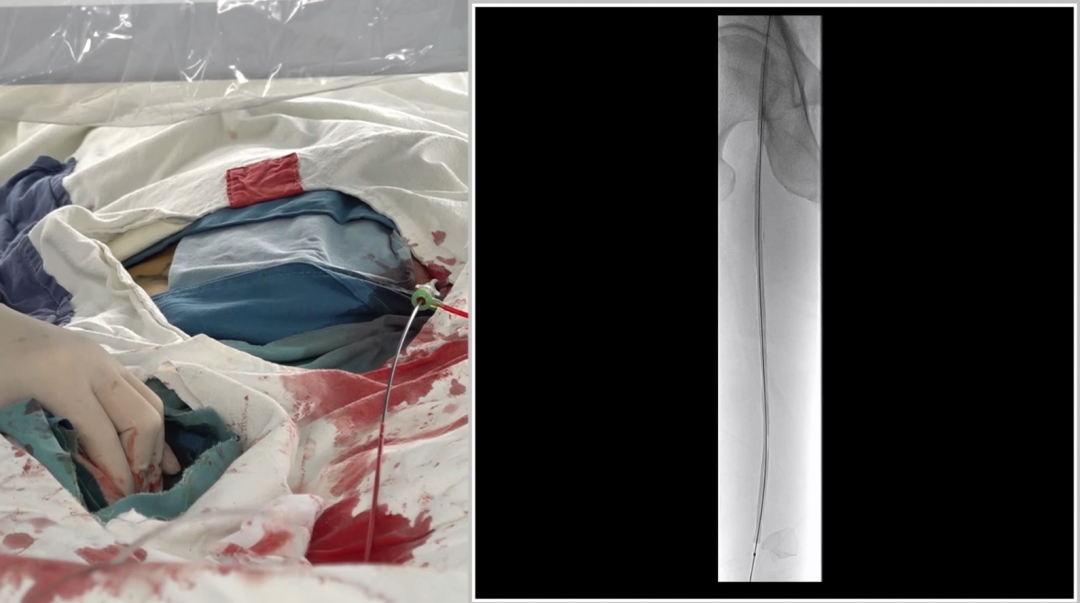

入路选择:左侧股动脉翻山入路

采用常规左侧股动脉穿刺,通过"翻山"技术到达右侧病变区域,为后续操作建立通路。

造影确认病变:长段闭塞,流出道尚可

造影显示右侧股动脉自起始段起长段闭塞,远端腘动脉及膝下动脉经股深侧枝显影,流出道条件尚可,为手术提供了基础。